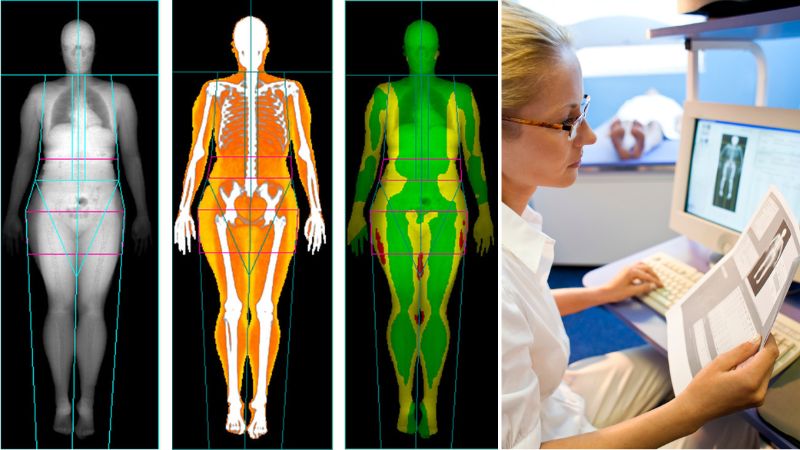

In contrast, DEXA provides a much more detailed breakdown of body composition. The machine uses low-dose X-rays to measure how two different types of energy pass through your body, ultimately providing an estimate of how the total mass of the body is divided across three components: lean tissue (muscle and organs), fat mass, and bone mineral content. These accurate metrics of bone mineral density, body fat percentage, total lean mass, total fat mass, BMI, and body composition in specific regions of the body go far beyond the simplicity of BMI, giving you and your healthcare provider a clearer picture of where your health is at.

There are many ways of finding out your body composition but none are as effective as a body composition scan. The scan generates a ‘fat shadow’ image showing the fat distribution in the abdomen, arms, legs and pelvis. Not only does a DEXA scan provide fast results, but it is also widely accepted as the gold standard for obtaining a comprehensive analysis of body composition.

DEXA scans use two low-dose X-ray beams that pass through the body at different energy levels. By measuring the absorption of each beam by the body tissues, DEXA can differentiate between bone mineral content, fat tissue, and lean tissue (muscles, organs, etc.). The results are highly precise and provide a detailed breakdown of body composition.

The scan process itself is very quick and easy. “In short, you lie on a table and the machine scans your whole body to assess your body composition,” explains Dr Du Plessis. “The scan takes about seven minutes and the radiation dose is almost nothing – it’s equivalent to 24 hours of background radiation at sea level. A report is then generated indicating the amount of muscle and fat in your body.”

Every patient at SCP Radiology receives a comprehensive radiologist’s report a few days after the scan. The report can be sent to your referring healthcare provider (whether that be your doctor, physiotherapist, surgeon, etc), as well as directly to you.